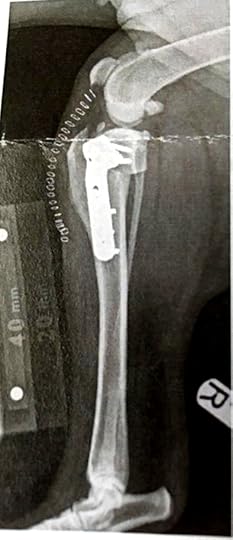

Monday was our appointment with Cookie at Liverpool University Small Animal Teaching hospital for her leg problem. The day started with us having to distract her while the other dogs were fed. There was a strong possibility of anaesthetic so she had to be starved from the previous evening but missing a meal for Cookie is never a good thing and she was definetly not a happy bunny.We have been very lucky with all of our dogs and this is the first time we've ever been referred to a specialist vets so this was all new to us. On arrival it was hard to not be impressed not only by the building but the warm welcome and professionalism of the staff. We completed some paperwork and then handed in our insurance details to the office who deal with all of the claim process for a small fee. From my point of view this is fabulous as I have very little experience claiming on any of our policies for the dogs and to be honest I had other things to worry about.Despite Cookie's obvious discomfort and lack of mobility she was still determined to try and play with every other dog in the waiting room and her tail continually span in typical helicopter fashion.After a short wait we were met by Tom Cox, the Vet who would be looking after Cookie and we followed into a bright modern consultation room. The notes had already been sent over from our own vets which helped in terms of what medication she was already on etc. We went through the history of the injury with Tom and he did a short examination of her. After this he said that he'd like to x-ray her to confirm his thoughts that this was indeed a rupture of the cruciate ligament. We left Cookie and were asked to return a few later to have a talk through the results.I don't think that we had any surprise when we returned to be told that this was what we'd feared. Tom took us through the x-rays pointing out the damage and then spoke to us at length about the options going forward. It was clear that we'd been referred here because of the hospital's expertise in dealing with this type of injury. After talking things through we had no doubt at all that we wanted Cookie to have the TPLO surgery as we feel this is the best outcome for her quality of life going forward.The hospital had already provisionally booked Cookie in for surgery pending her results and we left for home very sad and concerned but totally confident that she was in absolutely the best place she could possibly be...The video below is very informative and sent to us by a few friends on hearing about Cookie's injury which is very much appreciated.